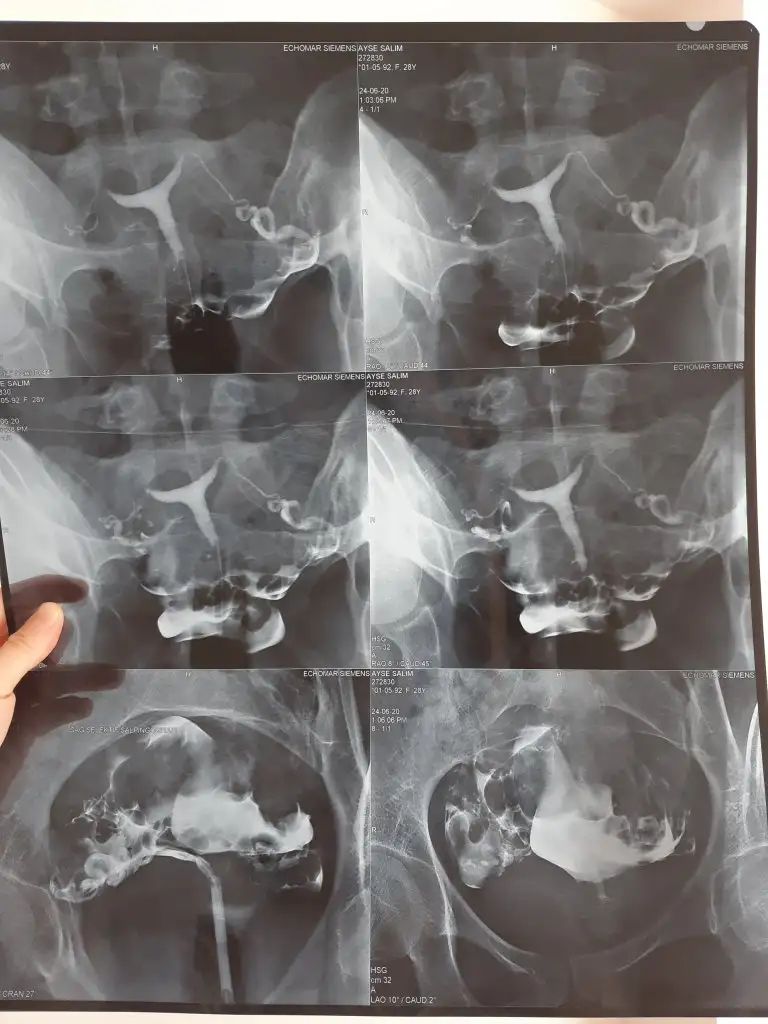

Merhaba, evet benim görüntüme çok benziyor 5 doktora gittiysem 3ü ameliyat dedi yaş ilerliyor zaman işliyor bende son çare olarak ameliyat oldum başka bi sorun gözükmüyordu tek engel T rahim olmamdı şükür oldum bitti çarşamba günü ilk kontrolüme gidicem. Ameliyat konusunda da doktorlar tamamen ikiye ayrılmış kimi ameliyat olman gerek diyor kimi gerek yok diyor 3.senenin sonunda ameliyata karar verdimMerhaba kızlar ben de bir dış gebelik iki düşük geçirdim bebekler 6.-7.haftada ölüyor doktor t rahimden dedi ameliyat önerdi korkuyorum zor muydu operasyon. Hsg görüntüm bu şekilde bir doktor bu küçük haftalardaki düşüklere neden olmaz dedi ama bu doktor direk görünce rahim normal değil dedi sizin hsg görüntülerinize benziyor mu acaba

Baya da doktora gitmişsin gerçekten de düşüklerin sebebi rahim şeklin gibi görünüyor ben hsg cekildim sonrasında ofis histeroskopi yapıldı tanı amaçlı doktor rahim dar genişletmemiz lazım dedi öyle karar verdik. Bu da benim rahim filmim12 doktor gezdim canım önce hsg ye gerek yok bir dış gebelik geçirmişsin abartıyorsun dediler sonra düşük yaptım hsg çektiler t rahimi gördükleri halde bu değil sebep kan pıhtılaşması dediler bir daha kalbi durunca da ya istersen işim garanti olsun dersen Rahmi düzeltelim dediler bu son doktor profesör hsg ye baktı doktor risk almış düşük olmasaydı bile erken doğum yapardın niye riske attı dedi çok zor günler geçirdim hala da geçiriyorum son kürtajı olalı iki gün oldu daha Rabbim kimseye yaşatmasın sana da çok geçmiş olsun Allah en hayırlısını nasip etsin inşallah

Evet benziyor canım inşallah çaresi budur Rabbim daha fazla acı yaşatmasın adet olduktan sonra yaparım operasyonu dedi bakalım neler yaşayacağız daha acılarımızın tekrarı olmasın inşallahBaya da doktora gitmişsin gerçekten de düşüklerin sebebi rahim şeklin gibi görünüyor ben hsg cekildim sonrasında ofis histeroskopi yapıldı tanı amaçlı doktor rahim dar genişletmemiz lazım dedi öyle karar verdik. Bu da benim rahim filmim